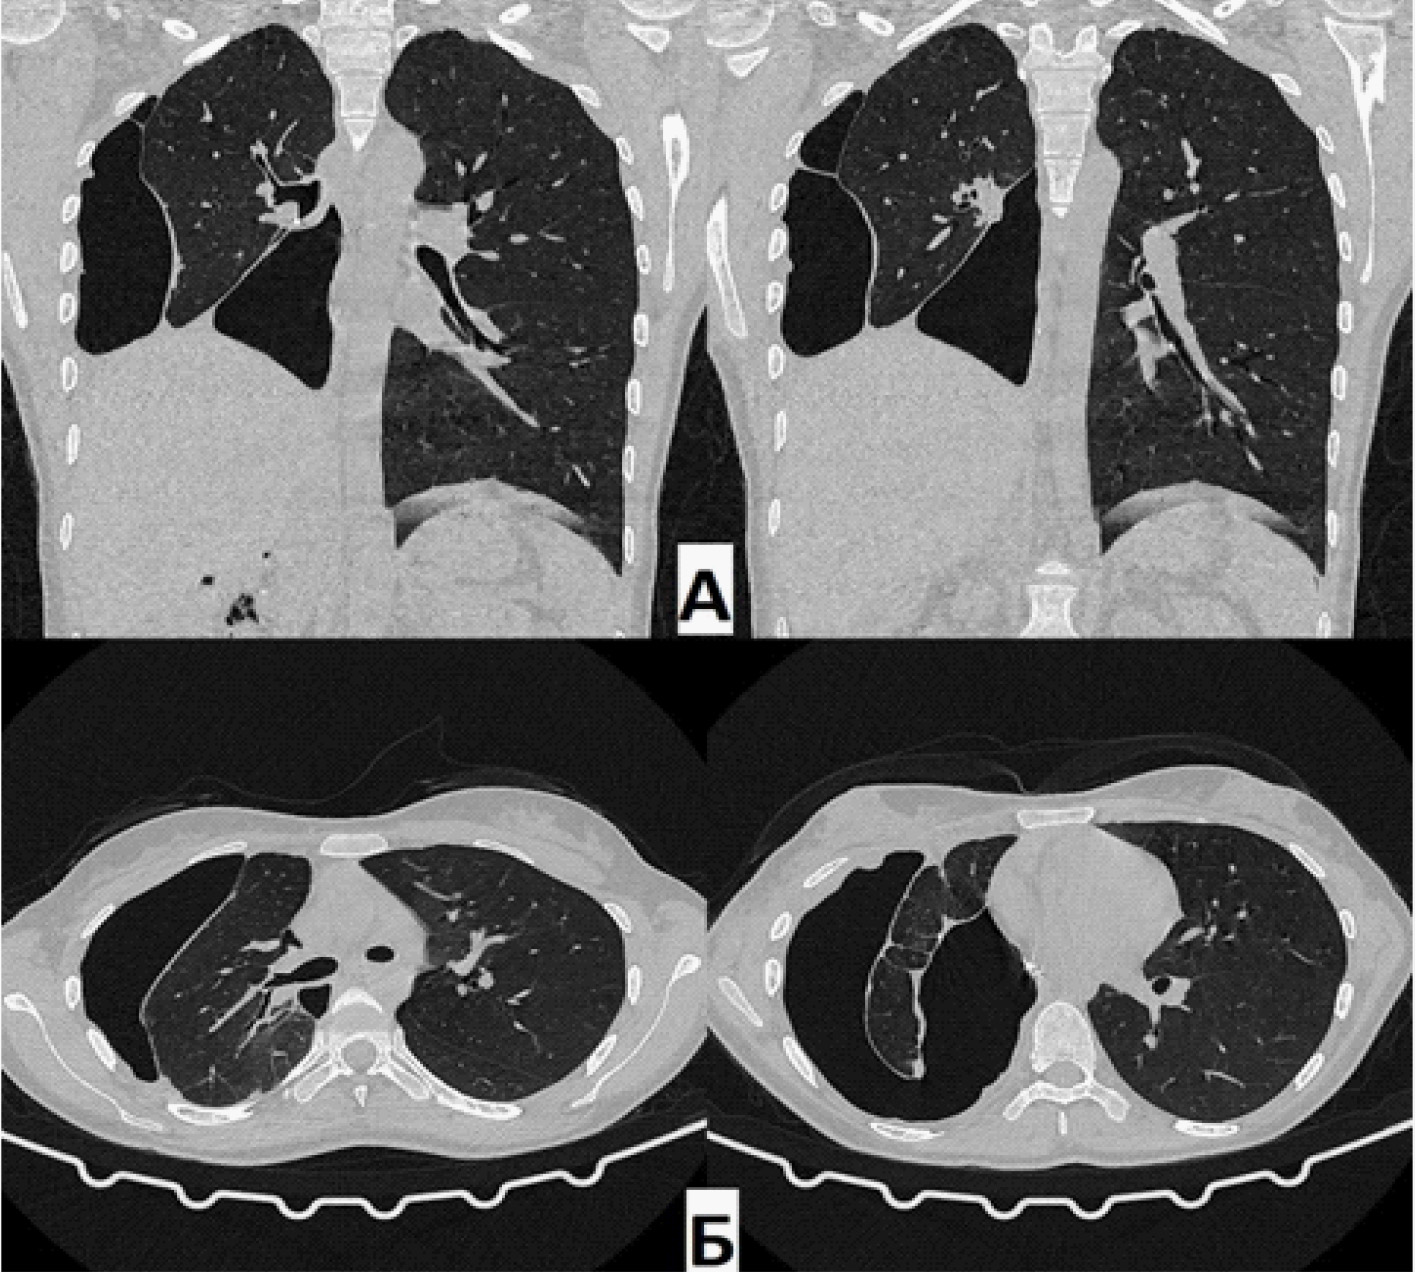

Через 1,5 месяца после операции пациентке выполнено КТ ОГК (07.09.2021.) (рис. 4): определяются косвенные признаки бронхоплеврального сообщения между культей правого промежуточного бронха и плевральной полостью, полость соприкасается с линией резекции культи (цепочки скоб). В динамике – увеличение объема ОПП в нижних отделах справа, как латерально, так и парамедиастинально. В оставшихся отделах правого легкого без свежих патологических изменений. Тень средостения располагается срединно, правый купол диафрагмы приподнят до уровня VI межреберья.

Рис. 4. Компьютерная томография (А – фронтальная проекция; Б – аксиальная проекция) через 1,5 месяца. Остаточная плевральная полость справа латерально и парамедиастинально. В динамике – полость увеличилась в размерах